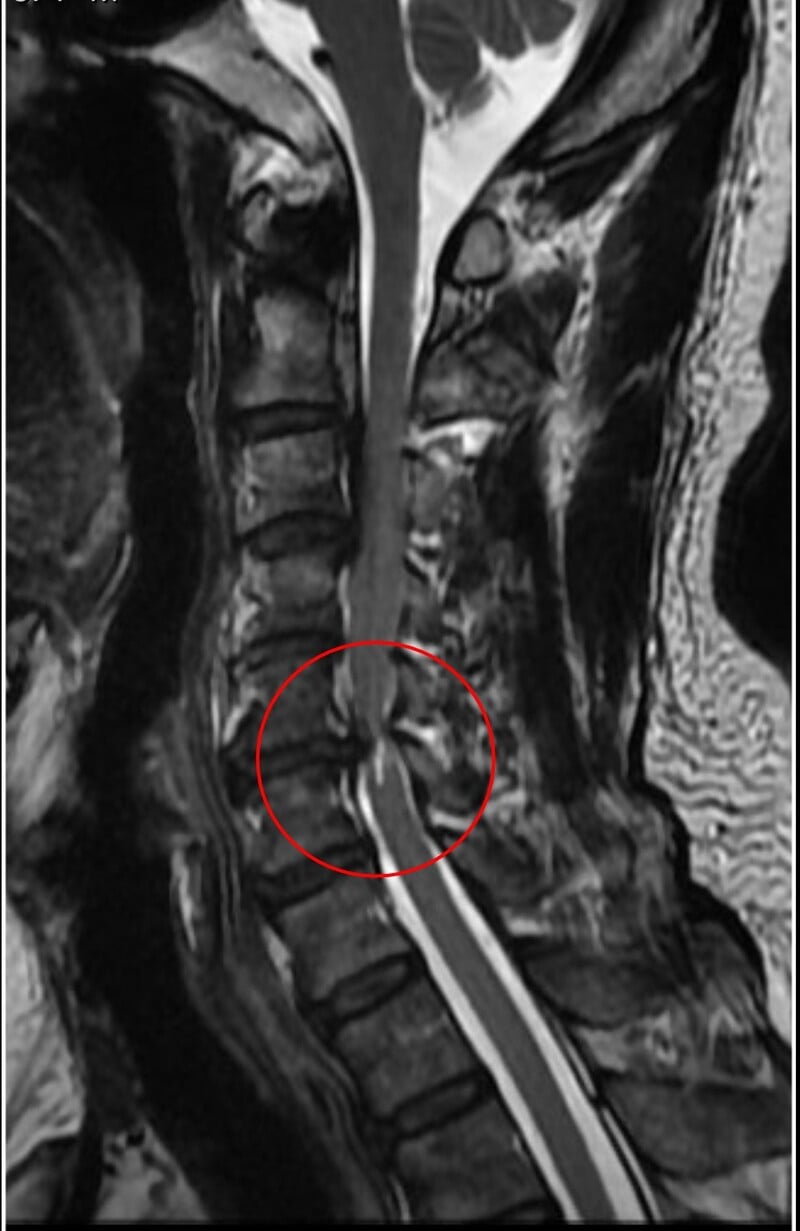

黃先生的頸椎第二節到第六節都有後縱韌帶骨化,其中第五、六節最為嚴重,脊髓已被壓得非常狹窄,核磁共振更可見明顯脊髓空洞,洪祥益主任說,這代表神經已受損,必須盡快手術,若再拖延,一旦跌倒、車禍或頸部突然甩動,都可能造成急性脊髓傷害,增加癱瘓風險。

相較一般骨刺可透過磨除方式處理,後縱韌帶骨化因質地硬且常與硬脊膜緊密沾黏,手術難度與風險顯著提高。洪祥益說明,手術過程需在顯微鏡下精細操作,避免損傷脊髓或造成腦脊髓液滲漏,此外,醫療團隊採取分階段治療策略,第一階段先由前側進行微創手術,直接移除壓迫神經的骨化組織,使脊髓獲得充分減壓;後續再規劃第二階段由後側進行椎板整形術,擴大椎管空間,以降低未來再度壓迫的風險。